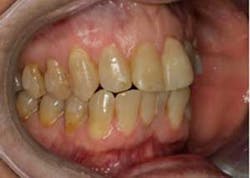

SFOT was used with a high-tech clear aligner to address hard- and soft-tissue deficiencies and severe maxillary and mandibular arch constriction.

A healthy, 57-year-old female presented with a lifelong desire for healthy, straight teeth and a beautiful smile. She had been told numerous times that it was not possible without premolar extractions.

SFOT surgery was performed in the maxillary and mandibular arches with deep buccal corticotomies. Particulate, demineralized, freeze-dried bone allograft and acellular dermal matrix were used to augment the ridges.

Total treatment time: 6 months. Patient declined recommended further clear aligner refinement and fine-tuning periodontal plastic surgery.